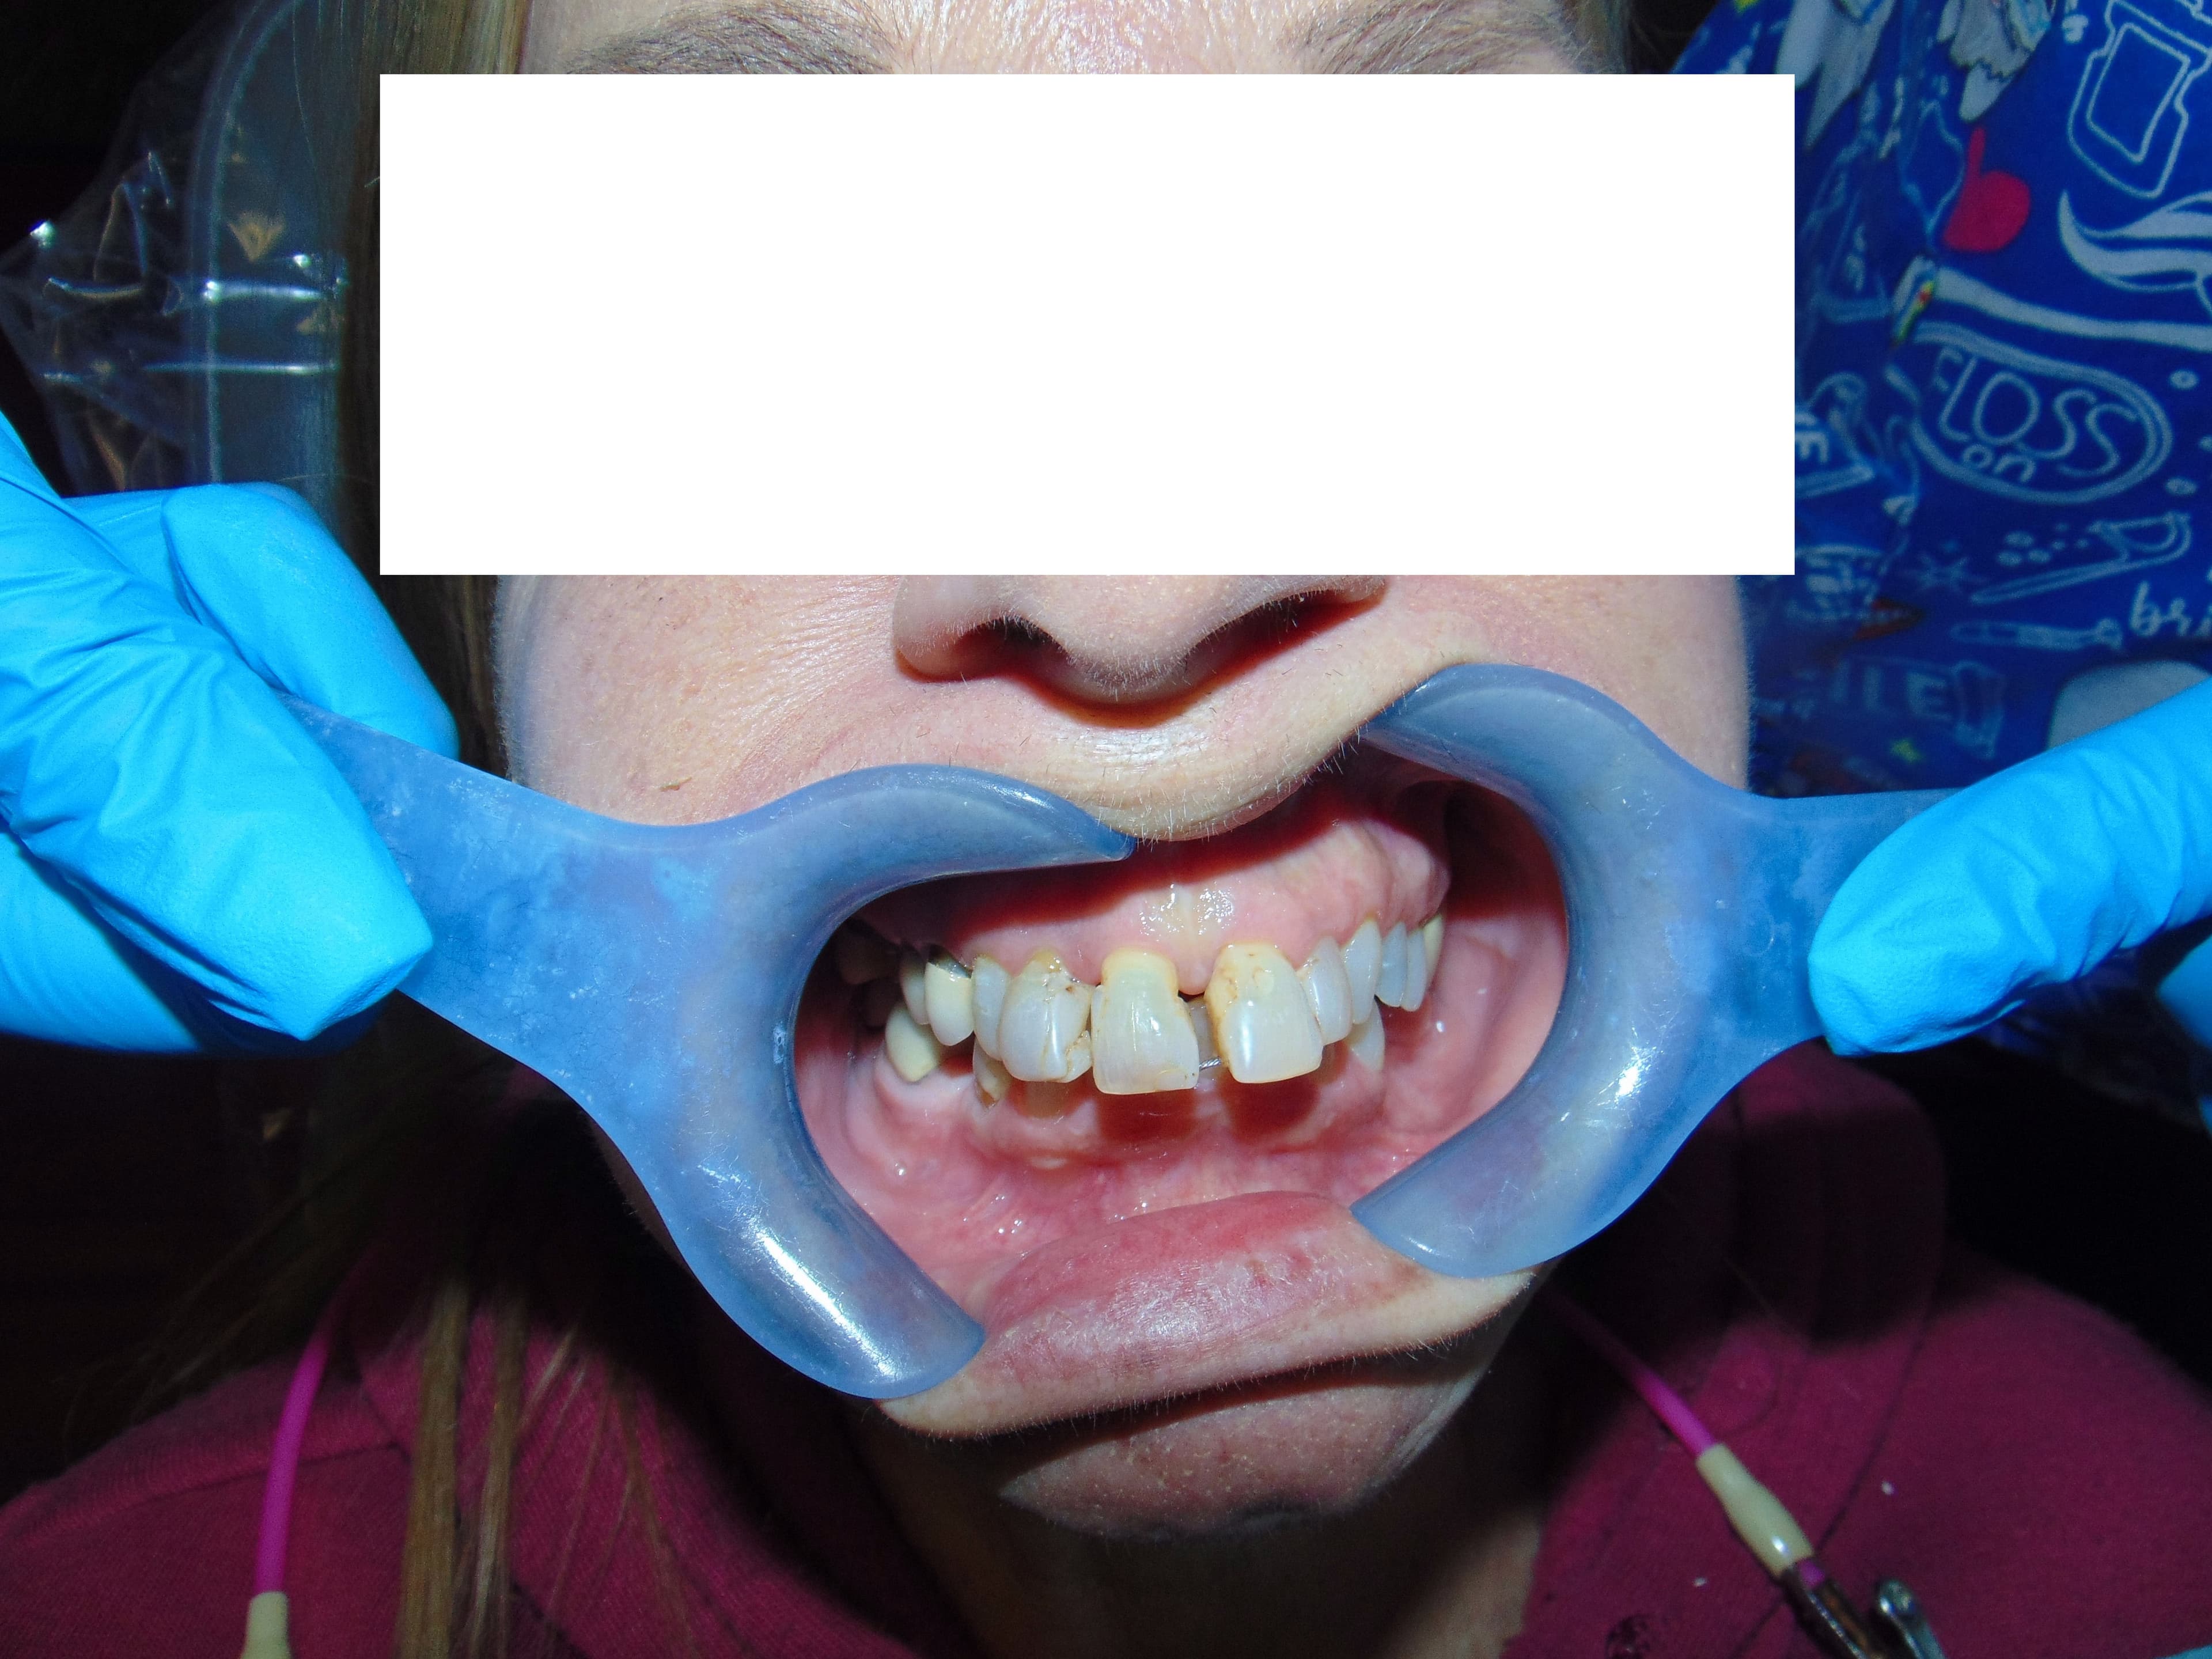

Case 12

58 yr old female with anterior splaying of upper teeth #7,8,9,& 10 due to periodontal bone loss resulting in total bite collapse and failure of wire splint and numerous bondings. Teeth #2,3,7,8,9,10 were extracted with selective bone grafting. Fabrication of transitional upper denture to be worn during the healing phase. Eight upper porcelain fused to metal crowns done to open occlusion approximately 3 mm to correct collapsed occlusion. Modifications were done to transitional prosthesis at each step to accommodate new crowns. Fabrication of upper valplast denture to complete restoration of upper dentition.